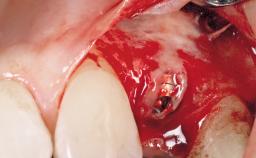

Immediate Flapless Placement of an Implant in a Maxillary Left Central Incisor Site

A 42-year-old female patient was referred to our clinic at the School of Dentistry of the University of São Paulo in November 2004, presenting a deficient restoration in the upper left central incisor. The clinical examination revealed no gingival retraction or any signs of gingival inflammation and, therefore, previous periodontal treatment was not considered. The patient presented a high lip line at full smile and a thin tissue biotype. This combination characterized a high-risk situation from an anatomic point of view, which required careful preoperative planning and cautious surgical execution.

| Placement Protocol | Immediate implant placement |

| Tooth Site | Maxillary incisor or canine |

| Socket Morphology | Single-root socket |

| Socket Integrity | Sufficient, with intact bone walls |